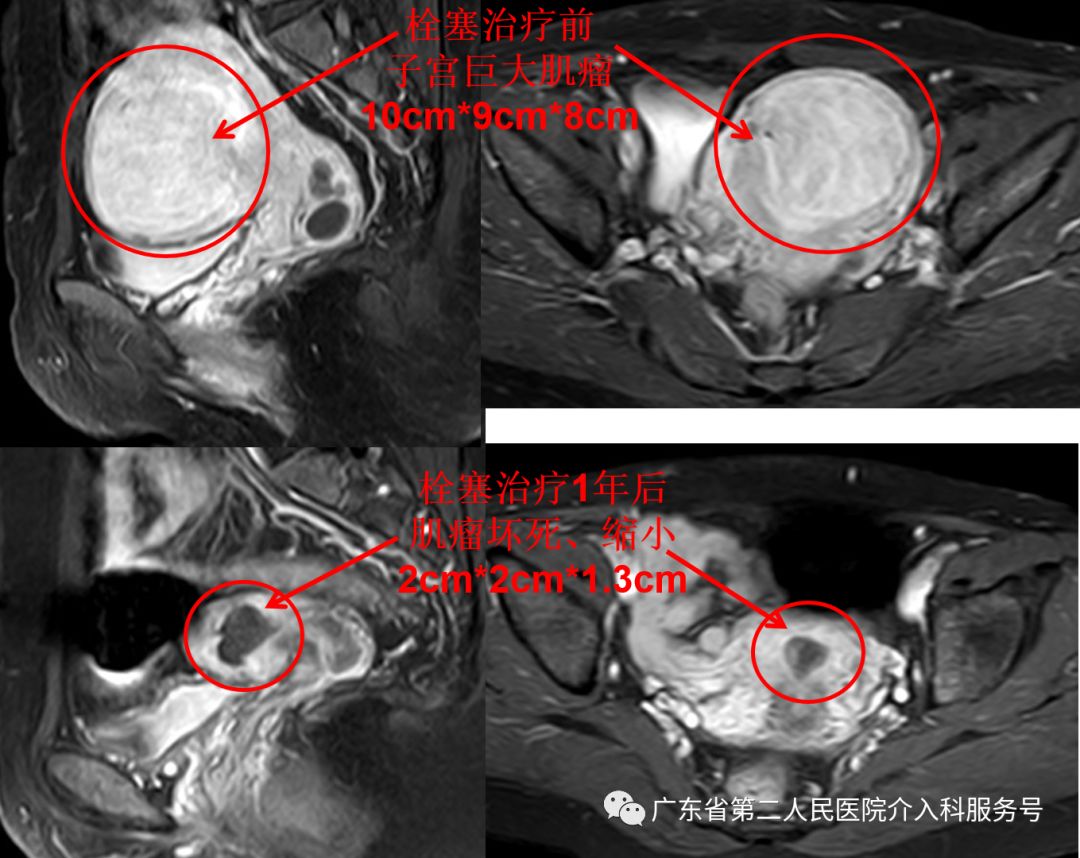

下图为梁女士的磁共振检查:子宫巨大肌瘤(国际妇产科联盟(FIGO)子宫肌瘤Ⅴ型,大小约10m*9cm*8cm)

治疗后差不多1个月,梁女士的“大姨妈”驾到,量正常,第7天即干净,再也没有淋沥不净的尴尬。3个月后,梁女士例假依然正常,已没有贫血貌,现在久坐后站立时再也没有出现眼前发黑(黑蒙)的现象。梁女士高兴的说:终于摆脱“大姨妈”来时排山倒海,大量血块,淋沥不净的烦恼,关键是可以和其他女性一样保留子宫,正常来月经,没有血块,不会淋沥不净,生活也舒坦了。门诊复查血红蛋白在正常范围,磁共振如下(子宫肌瘤已坏死、吸收、缩小(6cm*5cm*4cm),随后坏死的肌瘤还会继续吸收、缩小)。

1年后,梁女士例假依然正常,没有贫血。复查的磁共振如下(子宫肌瘤已坏死、吸收、缩小(2cm*2cm*1.3cm))。